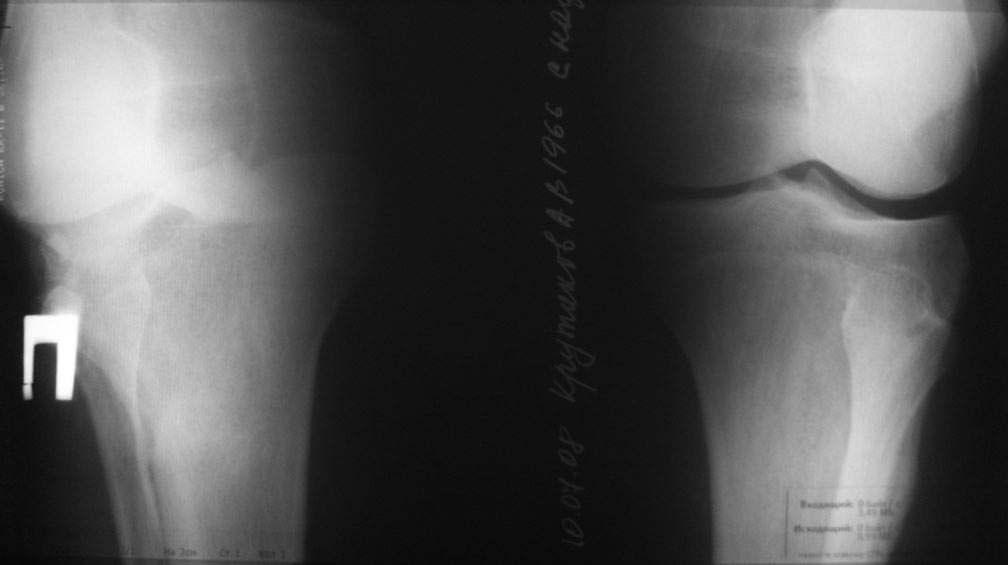

пациент наконец то объявился вновь и мы смогли выполнить новые снимки как лежа так и в нагрузке

если у вас остались силы, давайте обсудим